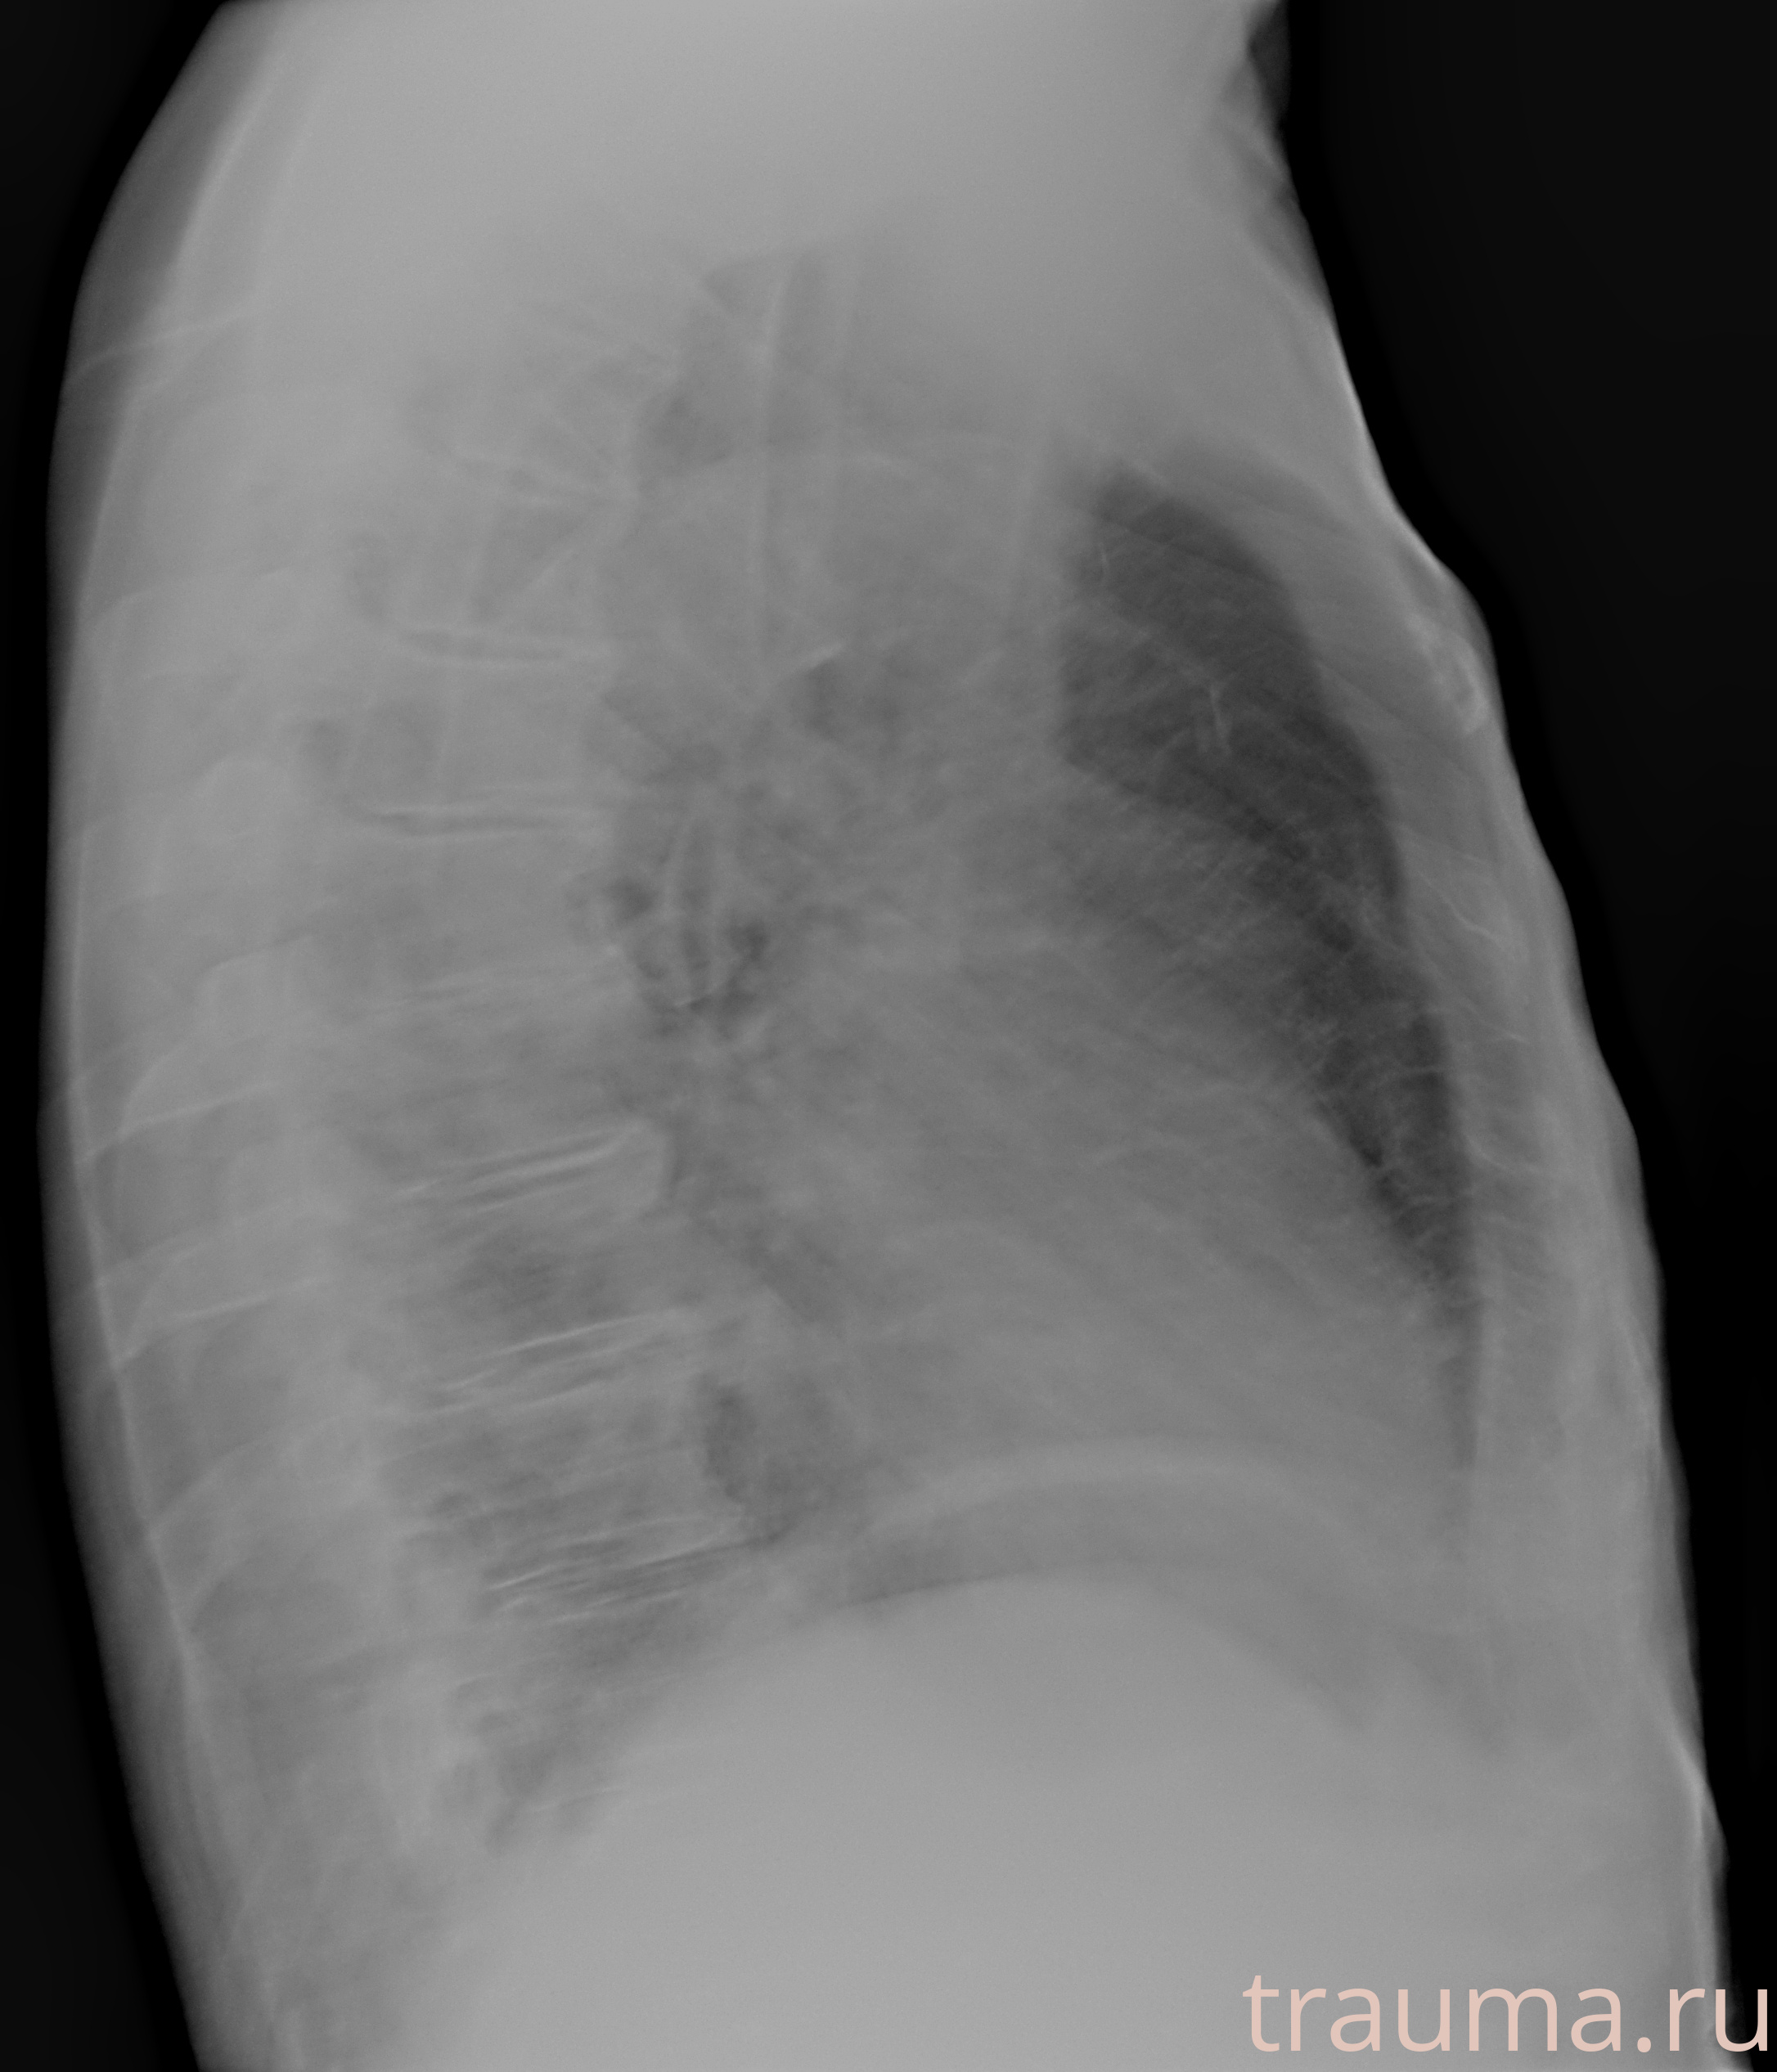

Рентгенограммы

Рентген на дому: по вашему адресу приезжает врач-рентгенолог, травматолог-ортопед с мобильным рентгеновским аппаратом, проводит диагностику травмы или заболевания, делает необходимые рентгенограммы, дает рекомендации по дальнейшему лечению. Получить качественные снимки в домашних условиях возможно благодаря уникальной методике, разработанной МосРентген Центром для института  Склифосовского